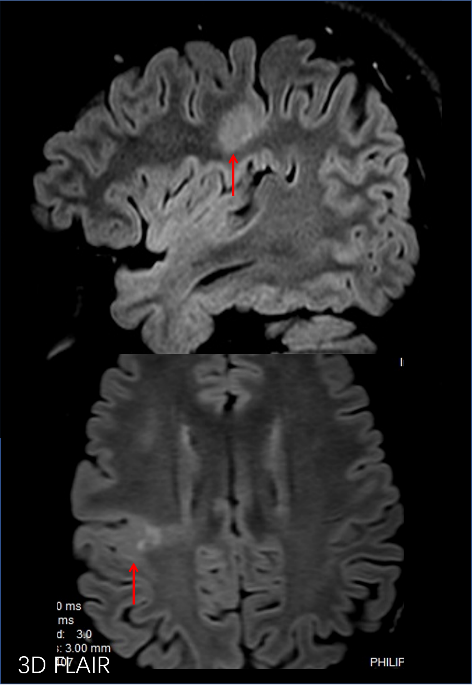

高分辨脑神经系统3D FLAIR成像技术显示局灶性皮质结构发育不良 高分辨脑神经系统mult-shot DWI 与传统single-shot成像技术对比,在脑灰质异位与急性脑皮质梗塞显示中更具优势。 3D SNAP-MRA 显示左大脑中动脉血管中断,3D FLAIR显示左脑萎缩及有功能的左手功能区,fMRI-Bold融合清晰显示功能区,DTI/FT 显示有功能的皮质纤维束。